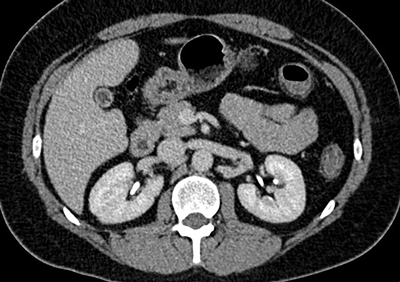

Figure 1: Coronal CTA demonstrating single renal artery supplying

each kidney and single vein draining each kidney.

Normal renal vascular anatomy (Figure 1)

Approximately 70% of the population have single bilateral renal arteries, originating from the abdominal aorta, at the superior margin of the second lumbar vertebral body, slightly below the superior mesenteric artery (SMA) origin [3]. The right renal artery orifice is located on the anterolateral wall of the aorta. The left renal artery originates slightly more inferolaterally than the right [2]. The typical dimensions of the renal arteries are 4-6cm in length and 5-6mm in diameter.

The renal arteries have slightly different trajectories, although both pass posteriorly towards the renal hilum. The right renal artery courses downward, and passes behind the IVC, while the left renal artery courses more horizontally and slightly upwards, posterior to the left renal vein. In the majority of cases the inferior adrenal arteries arise from the main renal arteries, and from the proximal aspect in two thirds of patients [2]. The main renal artery divides into segmental arteries approaching the renal hilum. The first division is typically the posterior branch, which passes posterior to the renal pelvis, to supply the posterior portion of the kidney. The remaining main renal artery then continues before dividing into four anterior branches at the medial aspect of the renal hilum: the apical, upper, middle, and lower anterior segmental arteries [4].There is no collateral arterial circulation between the renal segments; each of the segments is supplied by its own segmental artery [1]. Therefore segmental renal infarction will occur in the case of accidental segmental artery ligation.

Renal veins course anterior to the renal arteries. The segmental veins converge to form the main renal vein at the renal hilum [2]. The left renal vein usually receives the left adrenal, gonadal and lumbar veins before passing between the aorta anteriorly and superior mesenteric artery posteriorly, to enter the IVC. The shorter right renal vein, has no tributaries and enters the IVC at the level of first lumbar vertebra [3]. The right renal vein averages 2-4cm in length. The left renal vein averages 6-10cm in length [4]. In contrast to the segmental arteries there is free anastomosis of the venous system in the kidneys. This allows for ligation of the venous branches if a vessel is damaged during surgery, permitting an alternative venous drainage [1].